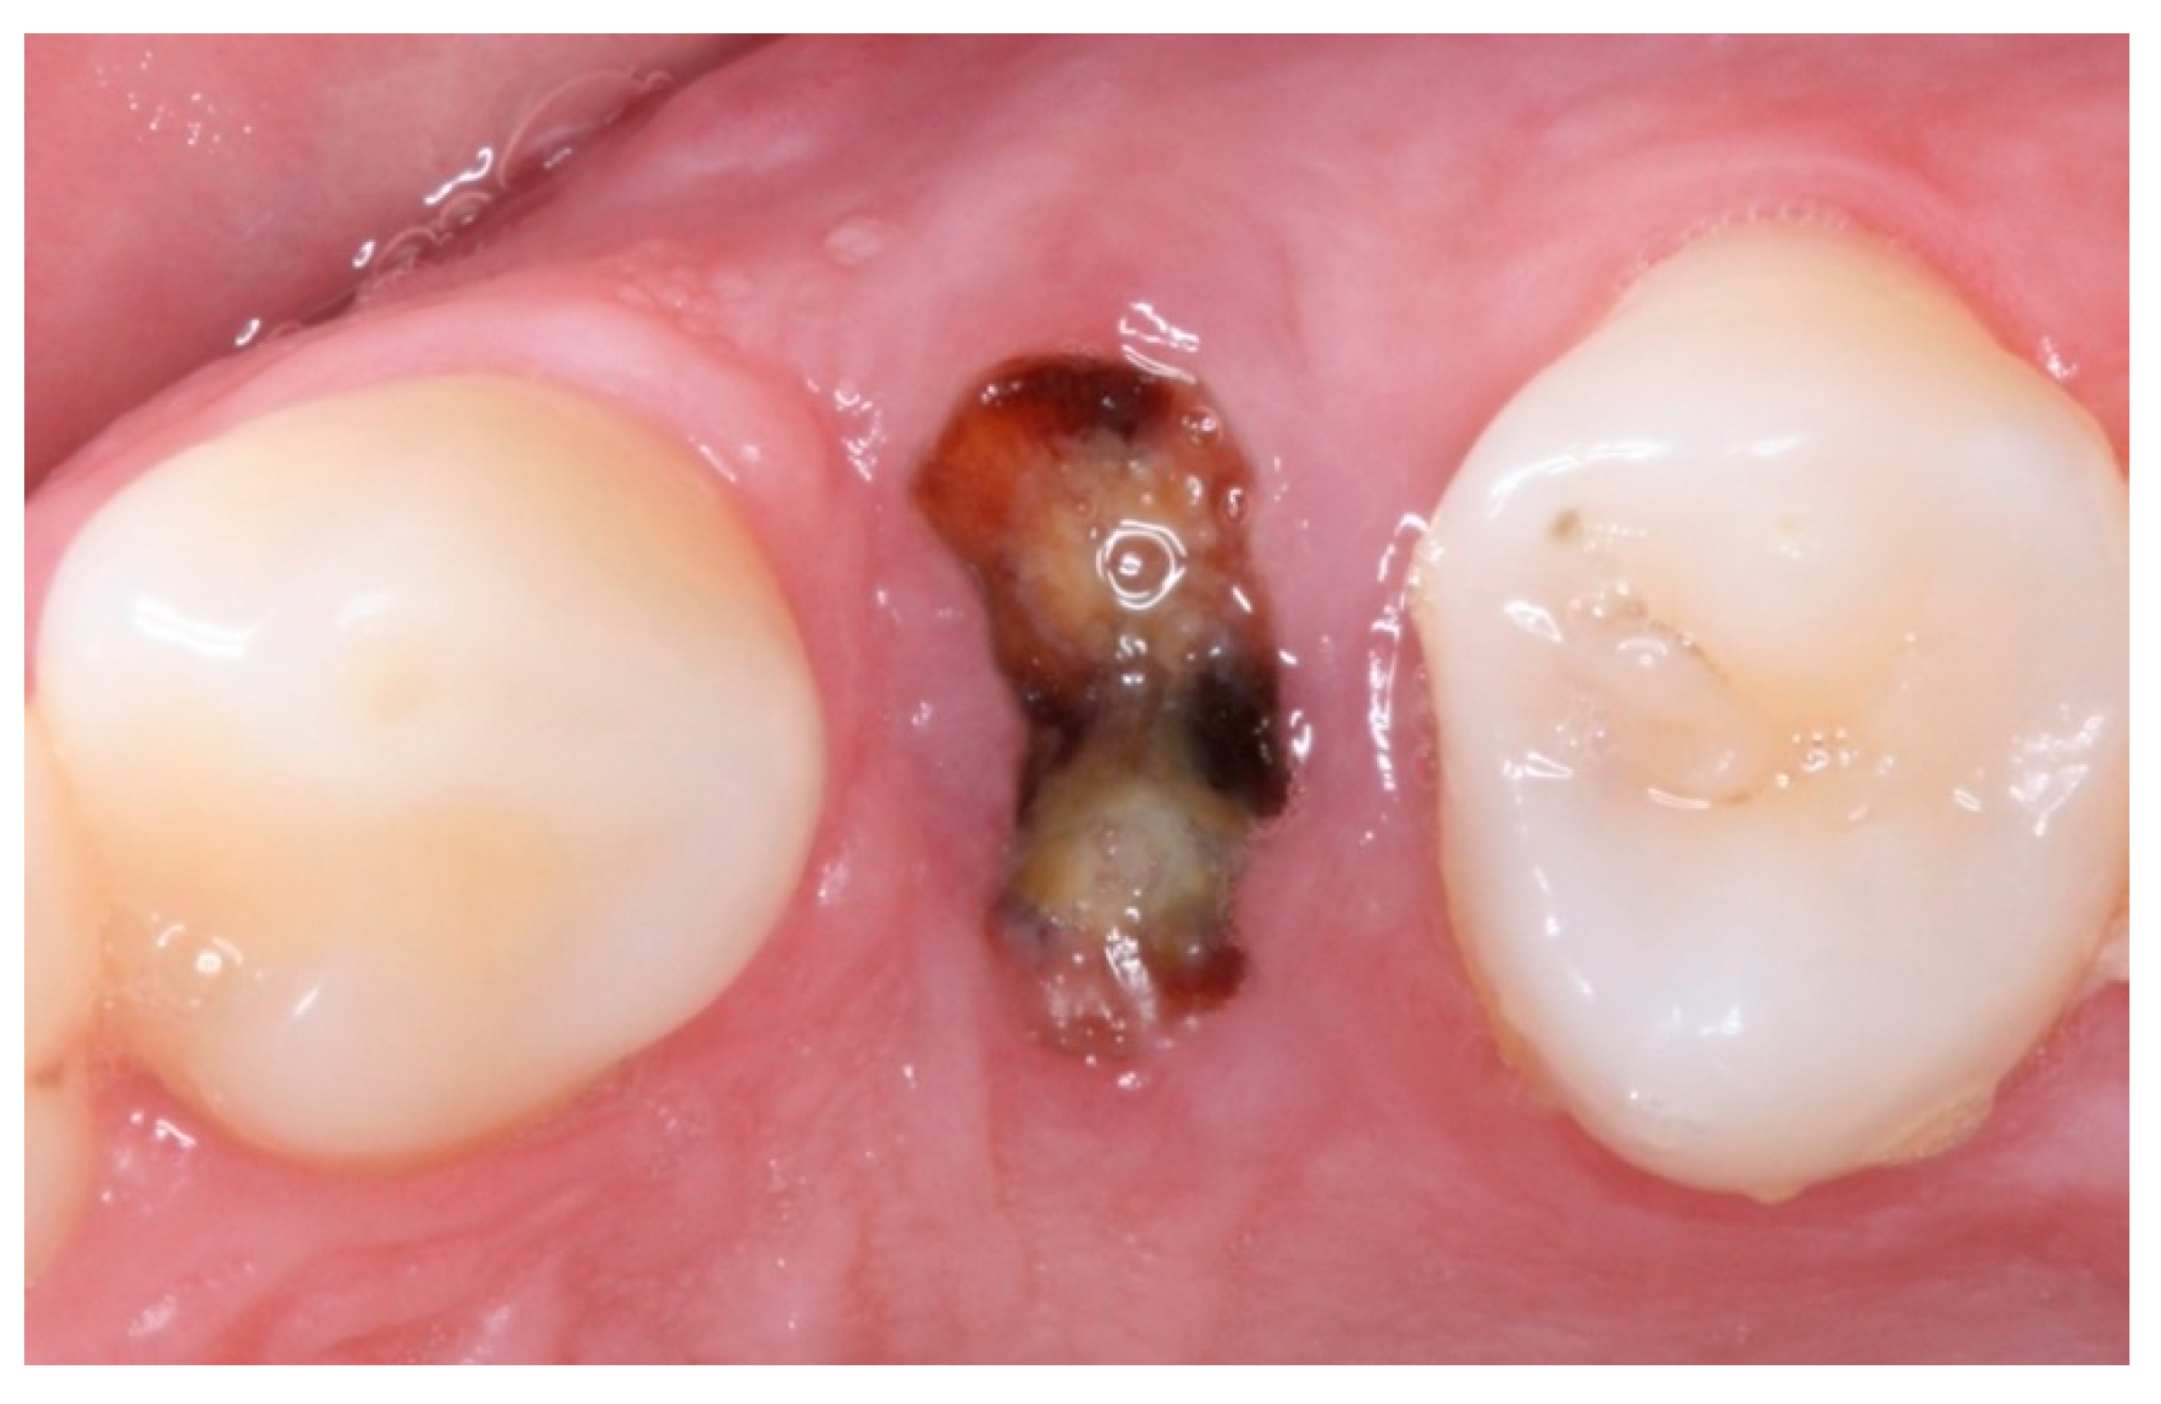

2. Materials and Methods

2.4. Groups